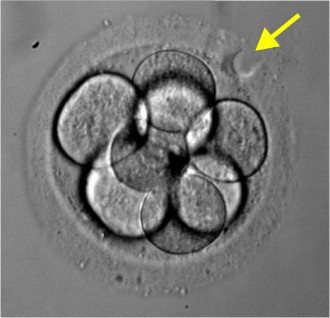

Tüp bebek neden tutmaz. Canım ben de menogon iğne ve klomen kullandım sadece 3 yumurtam oluşmuş çatlatma iğnesi verdi bugün olucam ertesi gün için aşılama dedi ama eşim aşılamayı istemiyor bizde kendimiz deniycez senin nasıl oldu bilgi verir misin. En az 3 tüp bebek tedavi girişiminde iyi kalitedeki embriyo transfer edilmesine karşın hamilelik oluşmaması ya da toplamda 10 ya da daha fazla embriyonun transferine rağmen hamilelik elde edilememesi tekrarlayan tüp bebek başarısızlığı diye adlandırılan bir durumdur. Mrb arkadaşlar menogon kullanan var mı ben ilk defa bu ay başladım daha 1 tane vuruldum bu iğneyle kaçıncı günde büyüdü yumurtalarınız ve bu yolla hamile kalanlar var mı forumlara baktım ama hep eski tarihli bende yeni bir konuda açmak istedim lütfen kullananlar bu forumda buluşalım.

Tüp bebek tedavilerinde hedeflenen nokta istenilen sayıda ve istenilen kalitede embriyo elde etmektir. Tüp bebek tedavisinde amaç. Tüp bebek kadına veya erkeğe bağlı kısırlık sebebiyle çocuk sahibi olamayan anne baba adaylarına uygulanan yardımcı üreme tekniğine verilen addır. Yumurtalıklar hap serophene gonaphene klomid klomen veya gonadotropin gonal f puregon menogon menopur fostimon merional adı verilen iğneler ile uyarılabilir.

Canımlar adetime az kaldı 3. İğne ile yapılan uyarıda daha fazla yumurta elde edildiğinden ve hapların rahim iç tabakası üzerine potansiyel olumsuz etkilerinden dolayı daha yüksek gebelik. Gonal f ve menogon kullanıp hamile kalanlar var mı. Kadından yumurta toplama ile elde edilen yumurta ve erkekten alınan spermin laboratuvar ortamında birleştirilmesi döllenmesi sonrası elde edilen embriyonun rahim içine nakledilmesidir.